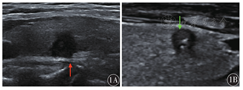

146例甲状腺乳头状癌患者中,病灶大小(1.11±0.65)cm,范围0.20~4.58 cm;纵横比1.13±0.29,范围0.58~2.44。左叶56例,右叶61例,峡部10例,双叶多发19例;超声显示甲状腺病灶与被膜分界不清62例(42.5%)(图1);实性141例(96.6%);内部回声均匀54例(37.0%);边界不清136例(93.2%)。内部钙化:无钙化34例(23.3%),微小钙化92例(63.0%),粗大钙化18例(12.3%),环周钙化2例(1.4%);内部回声:极低回声65例(44.5%),低回声79例(54.1%),等回声2例(1.4%);形态:形态规则24例(16.4%),成角13例(8.9%),分叶状6例(4.1%),不规则103例(70.5%);血流信号:0级21例(14.4%),1级103例(70.5%),2级15例(10.3%),3级7例(4.8%)。

甲状腺超声检查中达成共识的可疑恶性征象包括实性、低回声、形态不规则、边缘不规则、钙化缺损、纵横比≥1、微钙化、病灶向外浸润或累及甲状腺被膜等[9],虽然单独恶性征象均不能良好预测结节恶性风险,但每个超声特征的含义和诊断权重有所不同,如砂粒样钙化可降低假阳性率,极低回声强烈提示甲状腺恶性肿瘤[10]。研究甲状腺声像图中是否有与BRAF V600E基因突变相关的特征,以便从影像学的角度去判断甲状腺乳头状癌的侵袭性与预后,对于早期诊断很有意义。既往对于BRAF V600E基因突变与超声表现之间关系的研究结果有分歧[11],本研究显示,甲状腺乳头状癌的超声表现中病变与被膜分界是否清晰和BRAF V600E基因突变有关,结果与文献[12,13]的研究结果高度一致。BRAF V600E基因突变组中更多出现病变与甲状腺被膜分界不清,表明BRAF V600E基因突变与病变的侵袭性有关,提示在超声诊断中应该更加重视甲状腺结节与被膜分界是否清晰,当分界不清时对诊断甲状腺癌及判断预后更有意义。并且有研究表明甲状腺乳头状癌的三组亚型间是否靠近被膜与BRAF V600E突变之间差异有统计学意义[14]。也有研究表明BRAF V600E突变组甲状腺被膜侵犯出现得更少[15],但该研究中BRAF检测用免疫组织化学方法,与本研究的基因检测内容和方法不同。此外本研究4例滤泡状癌和1例髓样癌均未发生BRAF V600E基因突变,2例低分化癌都存在BRAF V600E基因突变,反映出的趋势是滤泡状癌、髓样癌不易伴随BRAF基因突变,低分化癌极易发生BRAF V600E基因突变,但病例较少,尚需进一步探索研究。